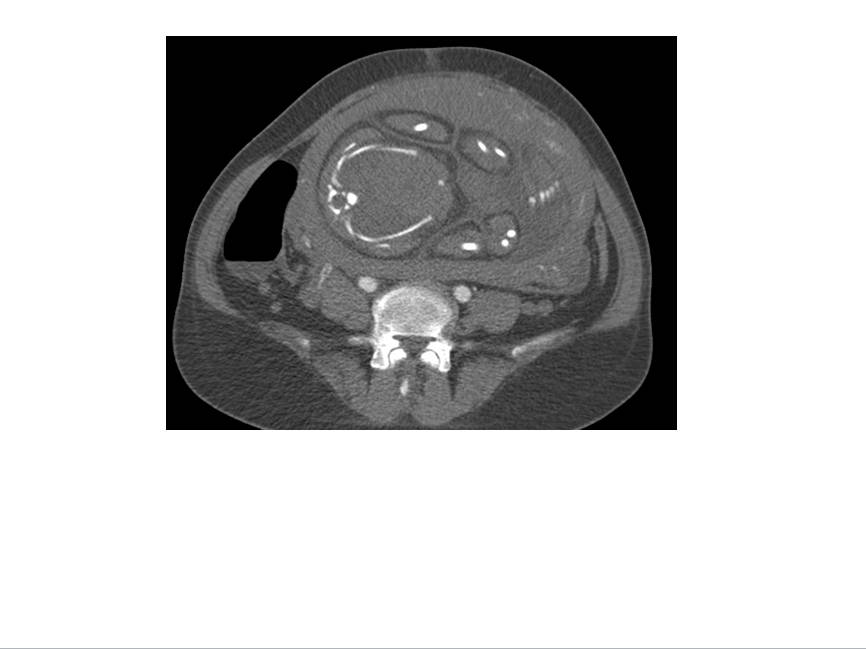

CT表现:自主动脉根部起至腹主动脉肾动脉水平可见撕裂之动脉内膜瓣影,子宫腔内可见胎儿影。

诊断结果:妊娠合并主动脉夹层(I型)。

1、撕裂的内膜瓣:多表现为弯曲的线样低密度影,部分患者可见多个破口,内膜漂浮在管腔中。

2、破口的显示:表现为真腔和假腔之间沟通的管道,薄层的横断图像,,多平面重组技术有助于破口的显示,有时因血栓的形成或撕裂情况复杂显示困难。

3、真、假腔的显示:真假腔可同时显影,或假腔强化和排空比真腔延迟;假腔内常有血栓形成可呈略高密度影,当多个破口存在时,真假腔较难区分。一般情况下假腔较大,真腔较小。

4、受累分支及范围:确认分支血管供血状况,观察主要器官的供血血管是发自真腔还是假腔。

显示冠状动脉、头臂动脉、腹腔内脏器动脉及髂动脉起源于真或假腔、是否受压推移。如果受夹层累及,可见内膜片线状充盈缺损影自血管开口处伸入分支血管腔内。